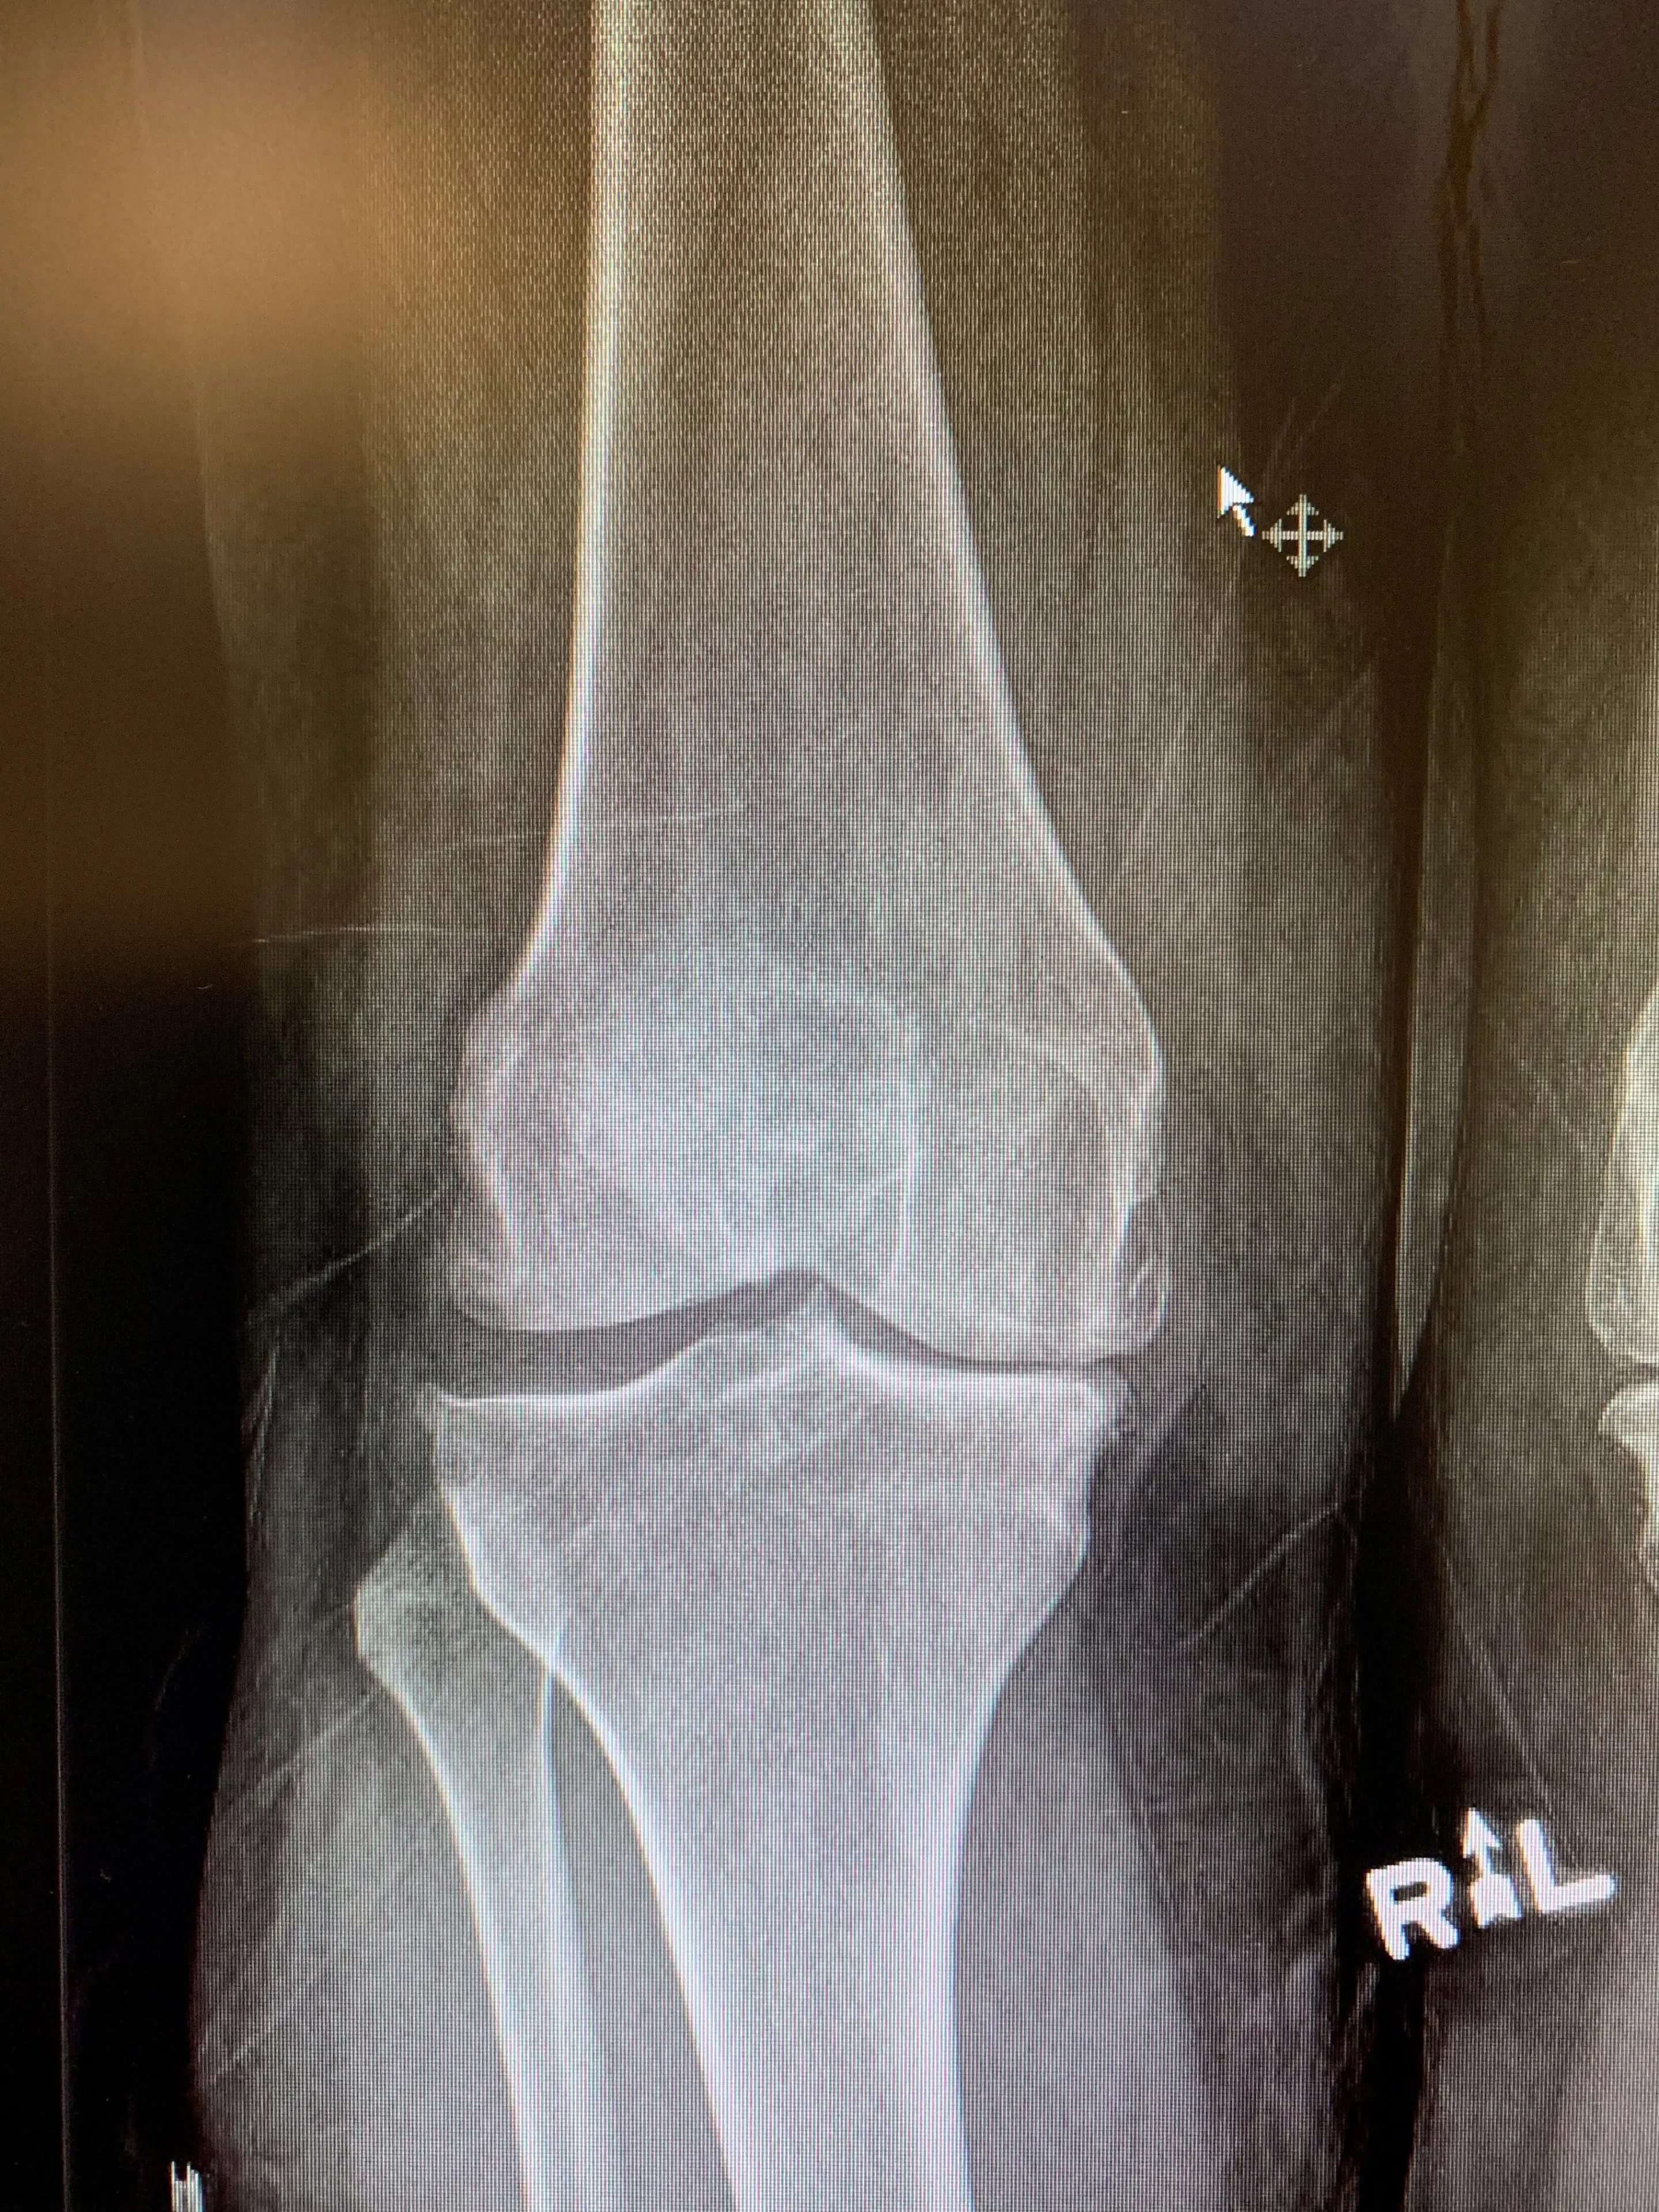

Her knee examination was unremarkable, although she was visibly uncomfortable during it. Her X-rays reveal varus osteoarthritis with significant posterior disease as compared to more anteriorly.

Pre op